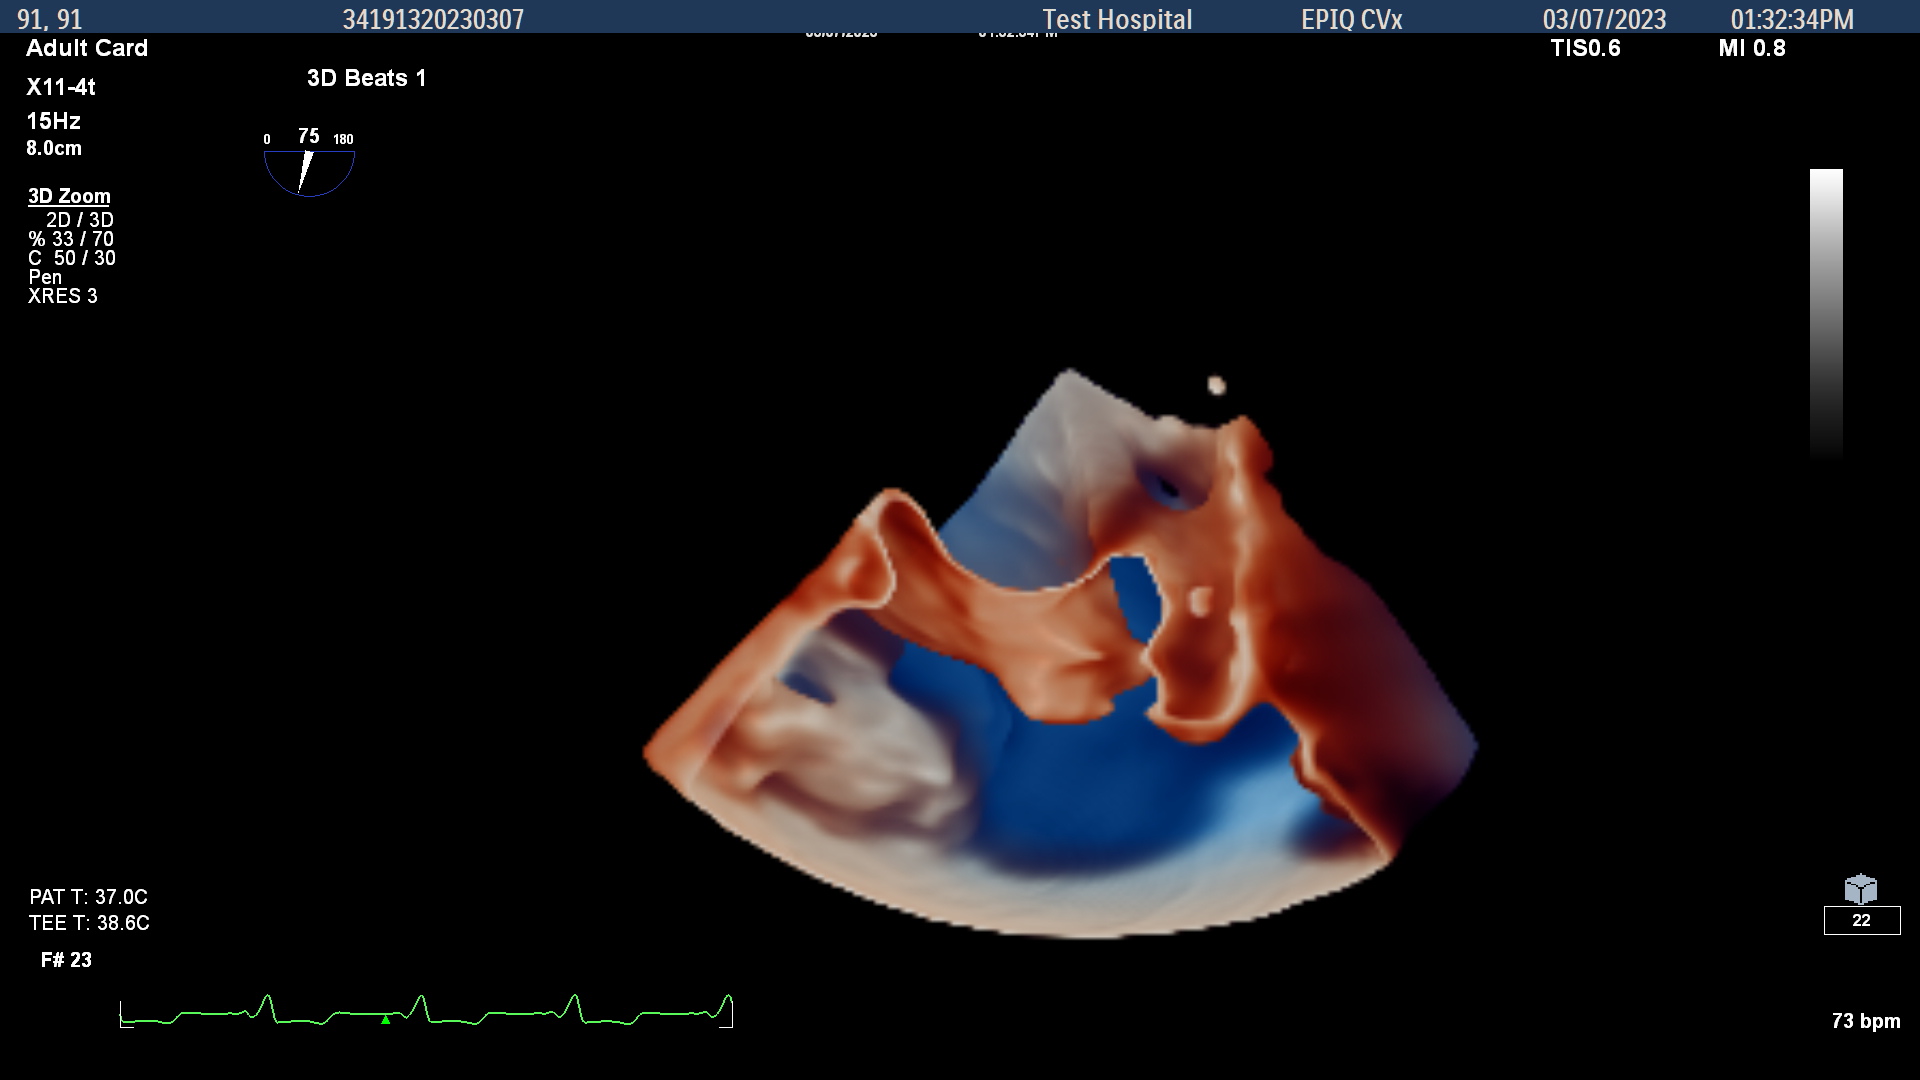

- As a pioneer and leading innovator in cardiac ultrasound, Philips has developed the smaller X11- 4t Mini 3D TEE transducer to serve more patients with this valuable imaging tool, from pediatric patients to older adults and everyone in between

Cardiovascular ultrasound has played a key role in the evolution of early diagnosis of structural heart disease, led by a technology pioneered by Philips: the ‘transesophageal echocardiography’ (TEE) ultrasound transducer. TEE helps cardiologists by providing highly detailed images of the heart and its internal structures. In structural heart disease, the quality of a 3D TEE image can help save lives. The clarity and perspective that come with 3D images exceed 2D alternatives. TEE is also a valuable tool for minimally invasive heart surgeries and procedures, transforming the treatment of damaged heart valves and congenital heart defects [2].

However, there were some patients who still couldn’t benefit from this advanced technology, including pediatric patients as small as 5 kg, adults at risk of complications [3], as well as complex cases such as ICU patients [4], where the transducer probe for 3D TEE was too large. Until now. Announced today, Philips’ new X11-4t Mini 3D TEE transducer is shifting that balance and opening 3D TEE imaging to previously unaddressed patients [5].

The new transducer is compatible with Philips’ premium cardiology ultrasound portfolio including the EPIQ CVx and EchoNavigator image-guided therapy solution, allowing clinicians to deliver personalized, efficient, and clinically smart cardiac care to help improve outcomes and the patient experience. It also joins a portfolio that includes another significant innovation – VeriSight Pro – the first 3D intracardiac echocardiography catheter to miniaturize the same 3D imaging technology that powers TEE.

- 3D View of young pediatric patient heart view

- 3D view of adult left atrial appendage